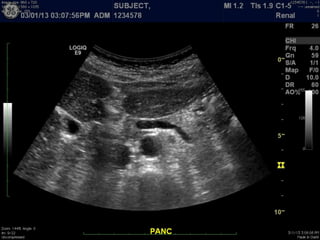

Modalities

B-mode, 2D imaging

A Primer ofDiagnostic Ultrasonic Imaging Modalities B-mode, 2D imaging